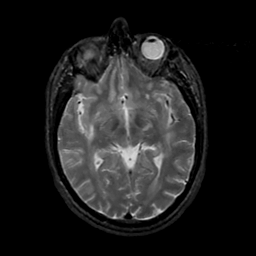

MR Study #17, July 7, 1991 -- Slice #23